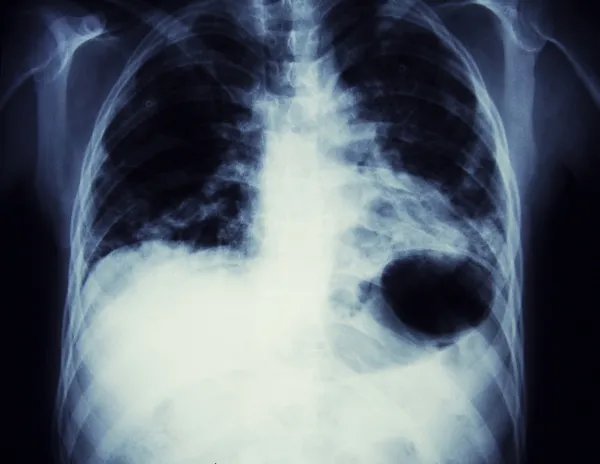

AKCİĞERİN OKSİJEN KAPASİTESİ DÜŞMEKTEDİR

Sigara içen kişilerin sadece kendilerine zarar vermediklerini söyleyen Aydın, "Tütün ve tütün ürünleri kullanan kişilerde; akciğer kanseri olma riski 22 kat, bronşit riski 10 kat, kalp hastası olma riski 3 kat, rahim ağzı kanseri riski 16 kat, prostat kanseri riski ise 2 kat fazla olmaktadır. Bununla birlikte sigara içen kişiler yalnızca kendi hayatlarını tehlikeye atmakla kalmaz, sevdiklerini de kendileriyle birlikte hastalıklara sürüklerler. Sadece 30 dakika boyunca sigara dumanına maruz kalan kişilerde kalbe giden kan oranı ciddi şekilde azalmakta, akciğerin oksijen kapasitesi düşmektedir. "Ben balkonda sigara içiyorum, kimseye zararım dokunmuyor" düşüncesi de sevdiklerinizi korumaya yetmemektedir. Saç ve giysilere sinen sigara dumanı aynı ev içerisinde yaşadığınız ya da aynı iş ortamını paylaştığınız sevdiklerinizi de pasif içici yapmaktadır" diye konuştu.